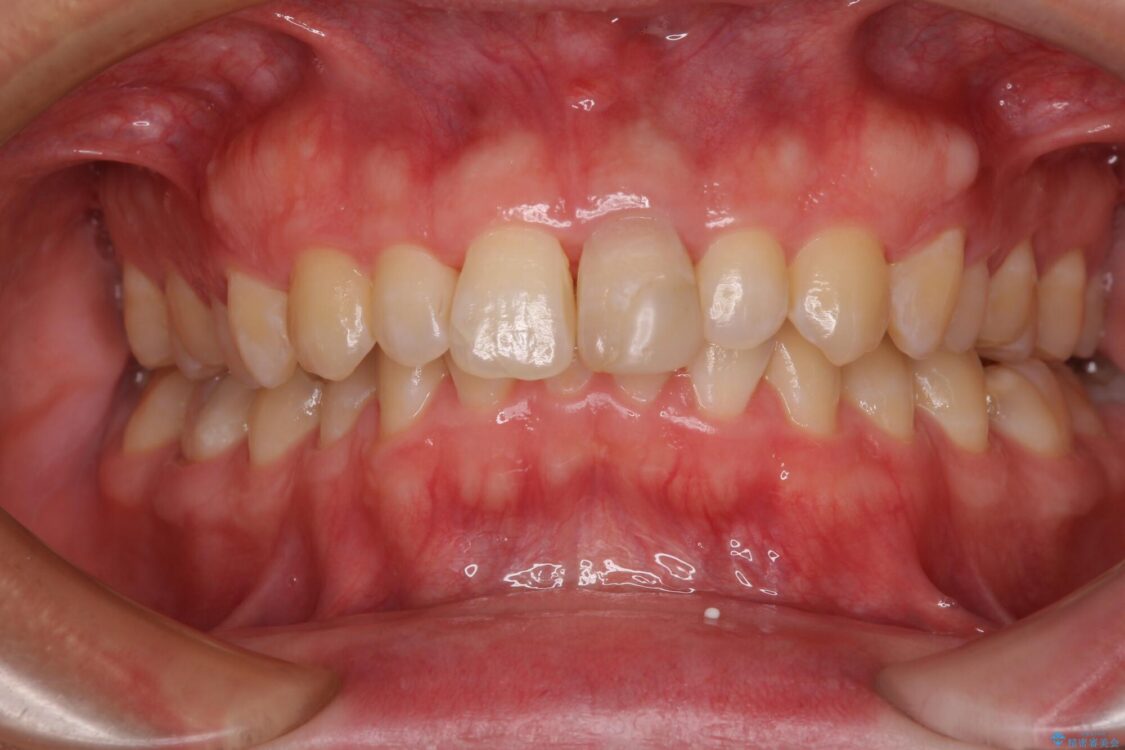

神経を取り除いたことで変色した前歯を気にして来院された患者様です。

根管治療はやり直さずに、ファイバーポストを使用した土台を植立してオールセラミッククラウンにて補綴することとしました。

治療前

• 変色した前歯をオールセラミッククラウンに 治療前画像